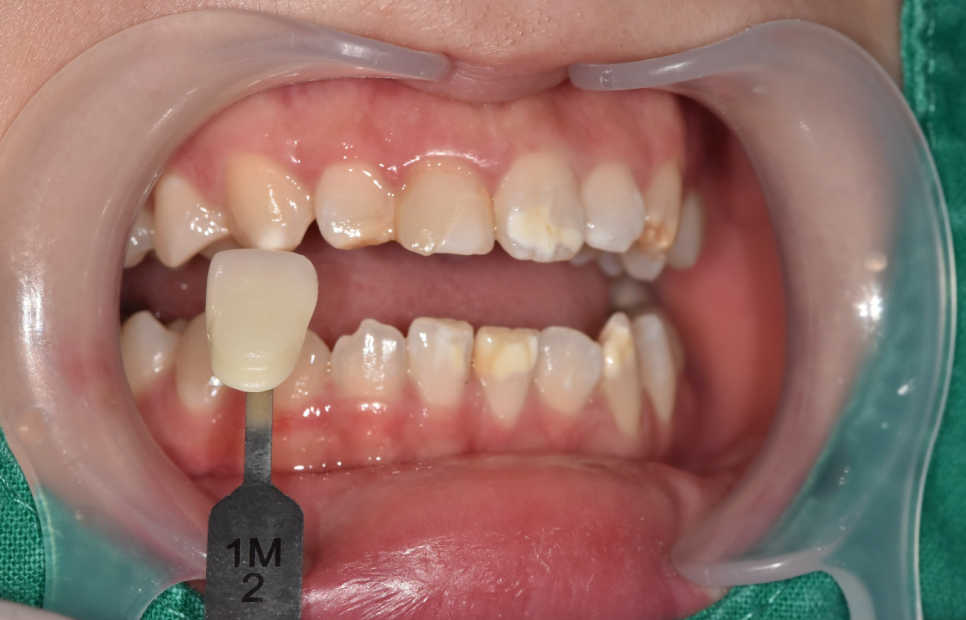

자연스러운 치아를 위해 옆 치아의 색상과 꼼꼼히 비교해 봅니다.

250503 강동구 라미네이트

옆 치아 색과 최대한 자연스럽게 만드는 게 핵심.

환자분과 충분히 상의해서 가장 자연스러운 색상을 선택했어요.